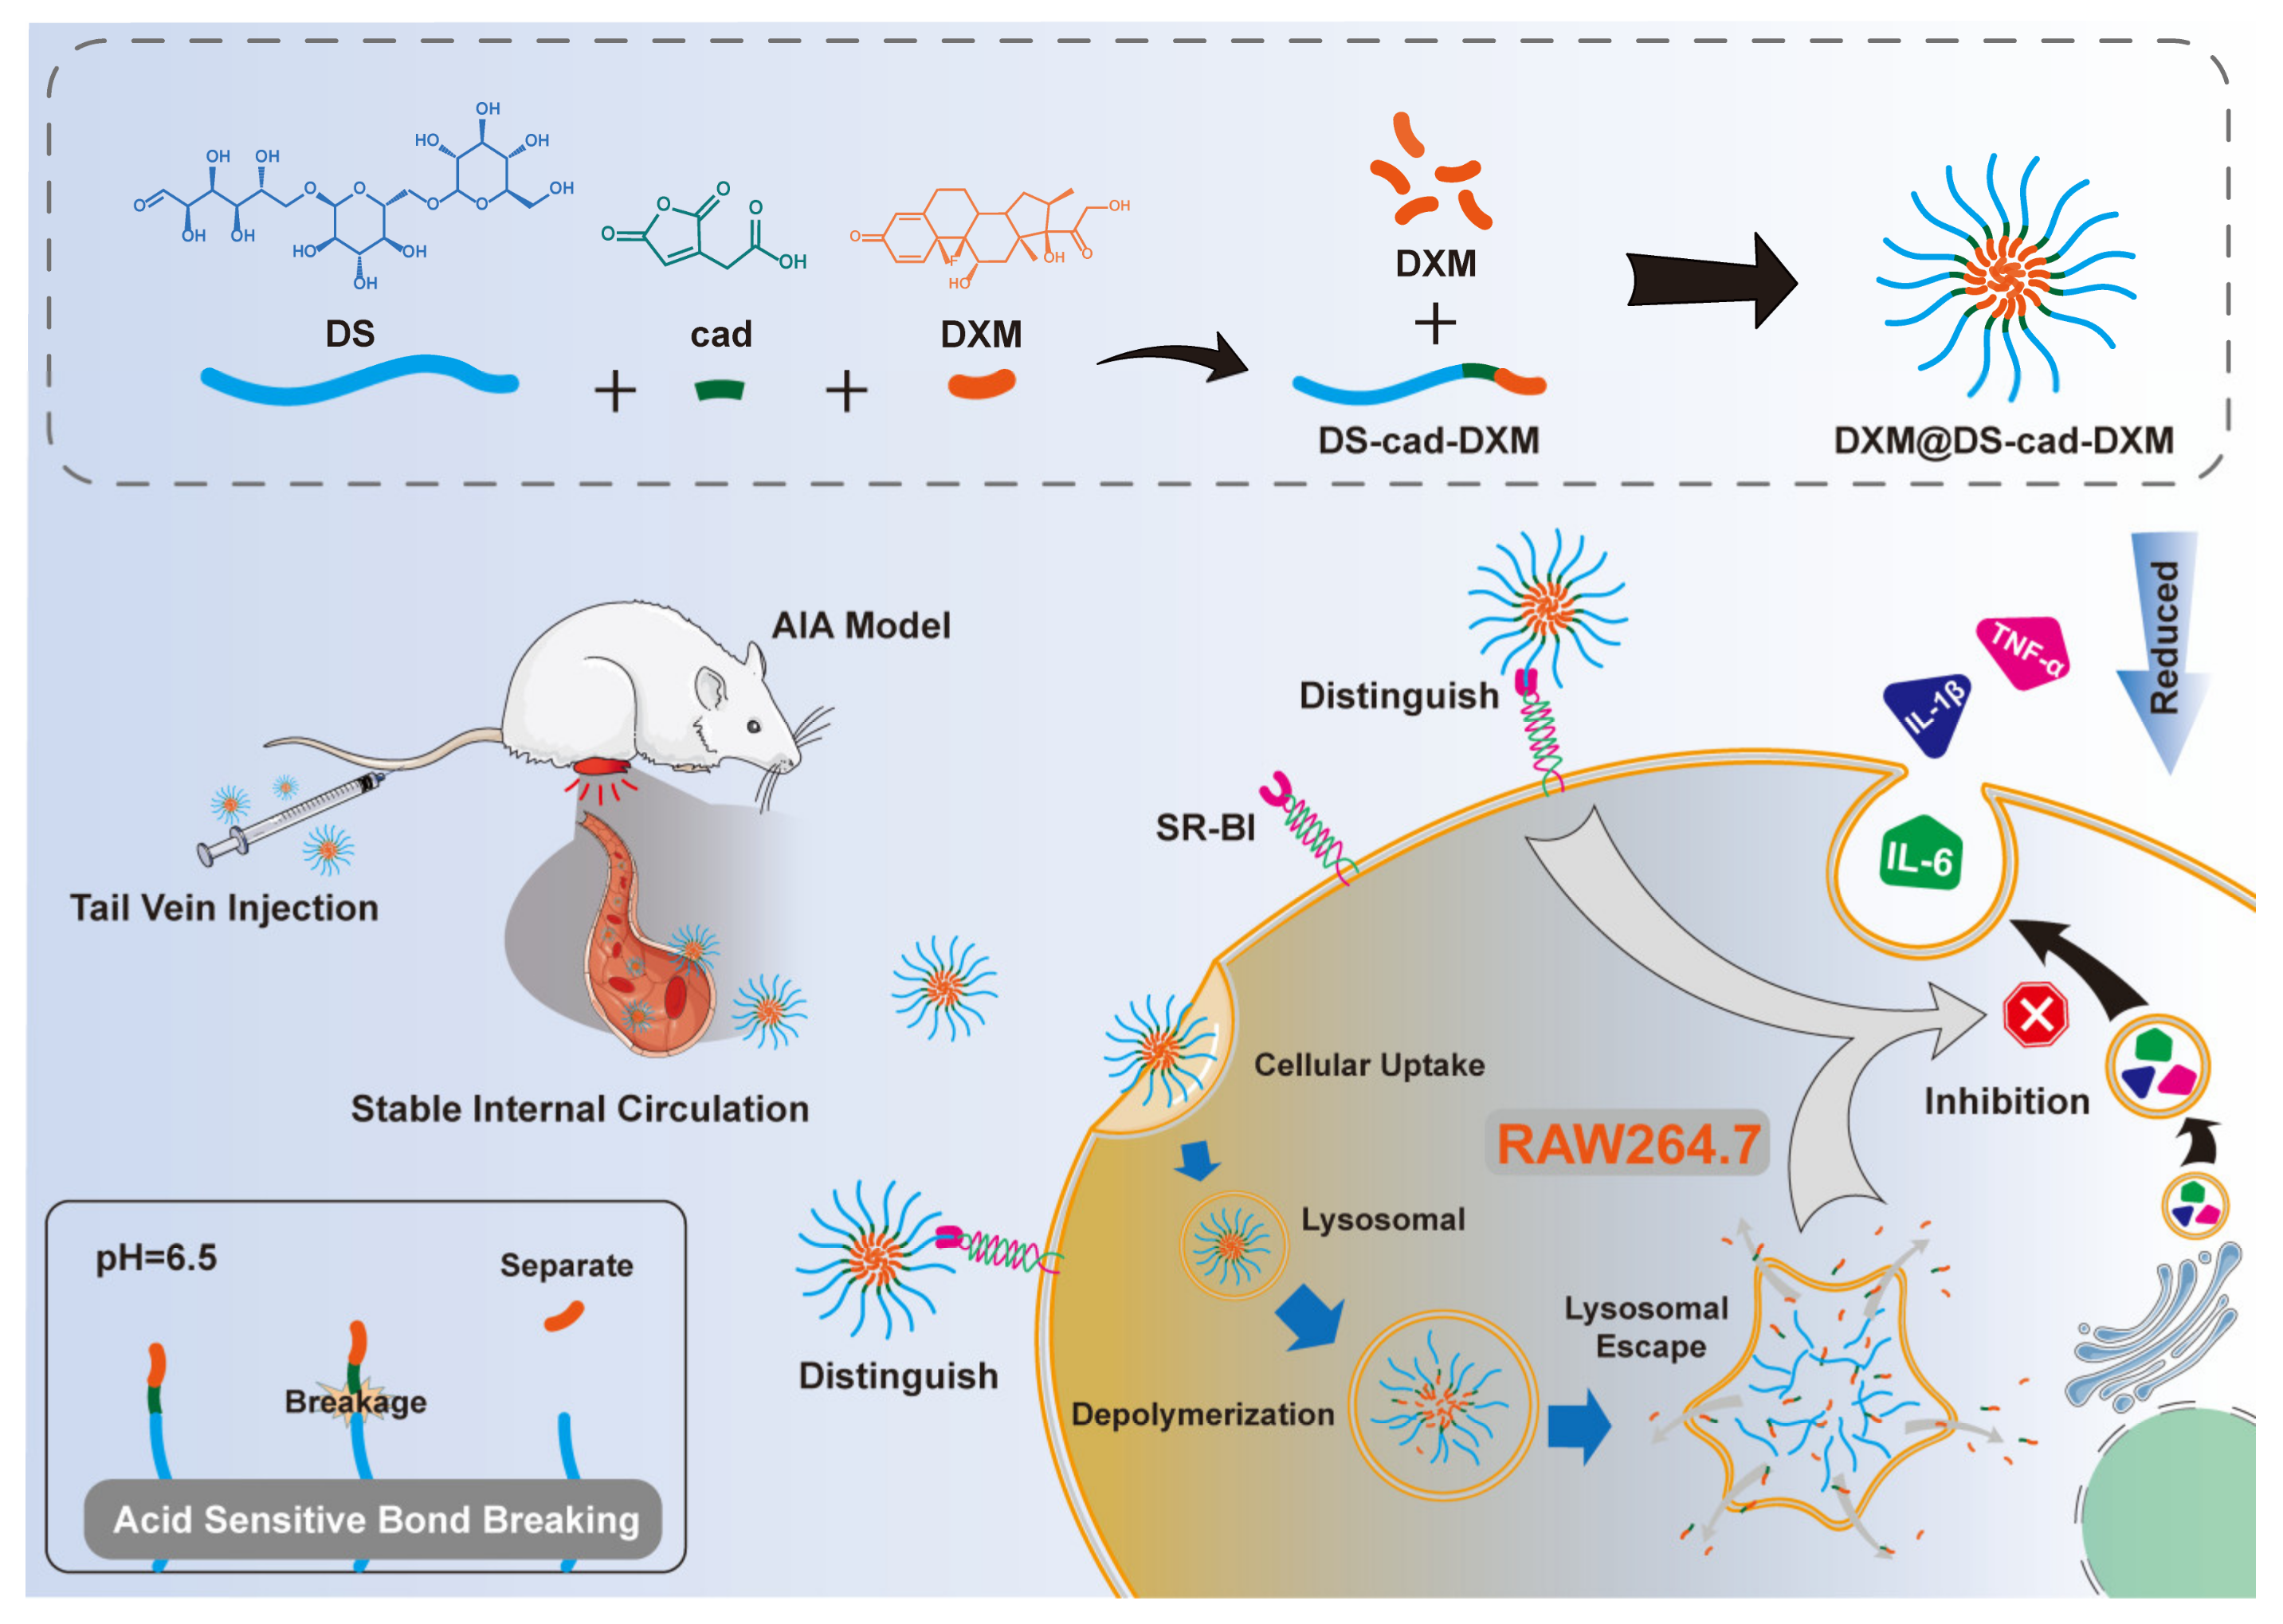

2. Results and Discussion

2.1. Characterizations of the Conjugates

2.2. Preparation and Characterization of Micelles

2.3. Release Profiles and Targeting Ability Analysis

2.4. Anti-Inflammatory Activity

2.5. Selective Biodistribution In Vivo

2.6. Therapeutic Efficacy of AIA Models

3.3. Syntheses of DS-cad-DXM Conjugate

3.4. Preparation and Characterization of DS-cad-DXM Conjugate Micelles (DXM@DS-cad-DXM)

3.5. Release Profiles of DXM from DXM@DS-cad-DXM

3.6. Biocompatibility Evaluation of DXM@DS-cad-DXM

3.7. Targeting Ability of DXM@DS-cad-DXM

3.8. Anti-Inflammatory Efficacy of DXM@DS-cad-DXM

3.9. Biodistribution of DXM@DS-cad-DXM

3.10. In Vivo Therapeutic Efficacy of DXM@DS-cad-DXM